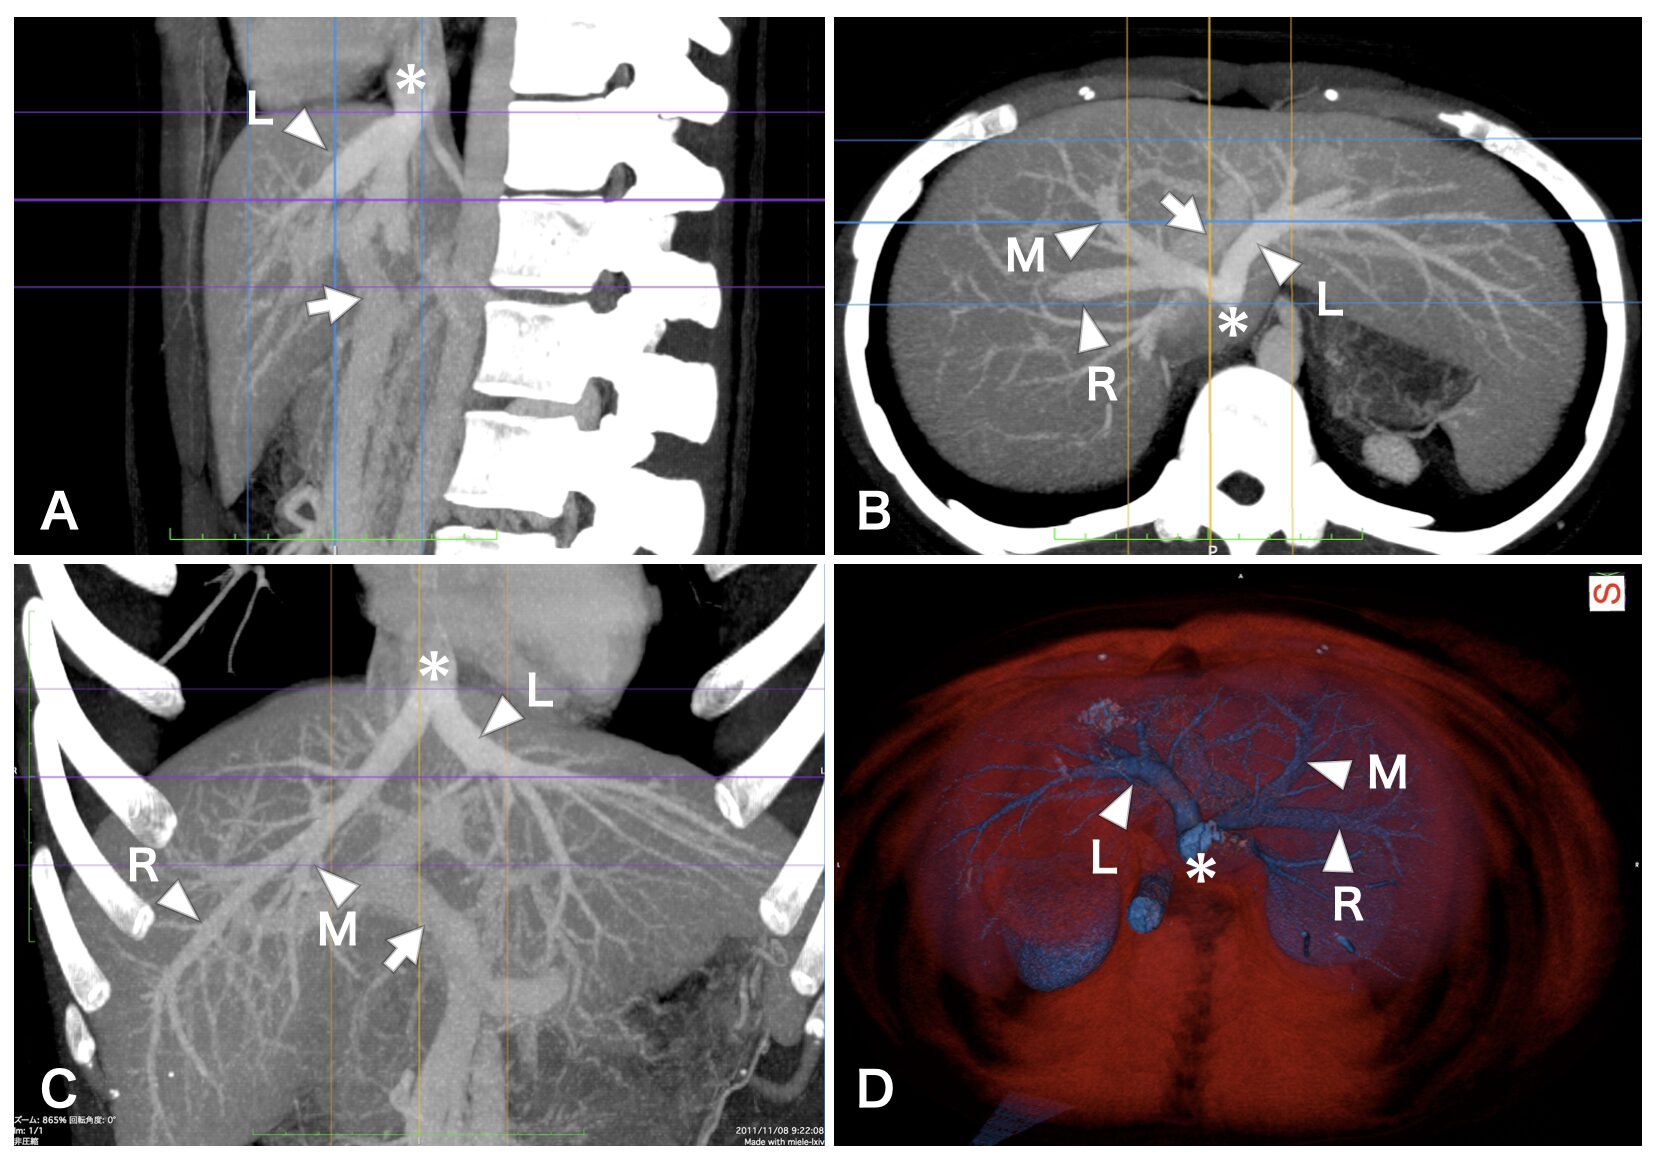

下に図の作例を示します。腹部のパートのCTで、肝区域の剖出をがんばったので、そのスケッチに対応づけるための図、という想定です。Pagesを使ってCT画像をレイアウトし、文字と記号を入れました。心臓、脾臓、胃、大動脈、腎臓なども写り込んでいるので、オリエンテーションのためにそれらにも適宜ラベルを入れてもよいです。説明文中で、➡、▶、*は、それぞれ、矢印、矢尻、アスタリスクと、名前にしてもよいです(本物の原著論文ならそうします)。

図1 造影CTから肝静脈を描出した。A~C、MPR像(Thick slice)。D、VR像(頭側から、骨除去)。R・M・L、右・中・左肝静脈。*、下大静脈。➡、門脈